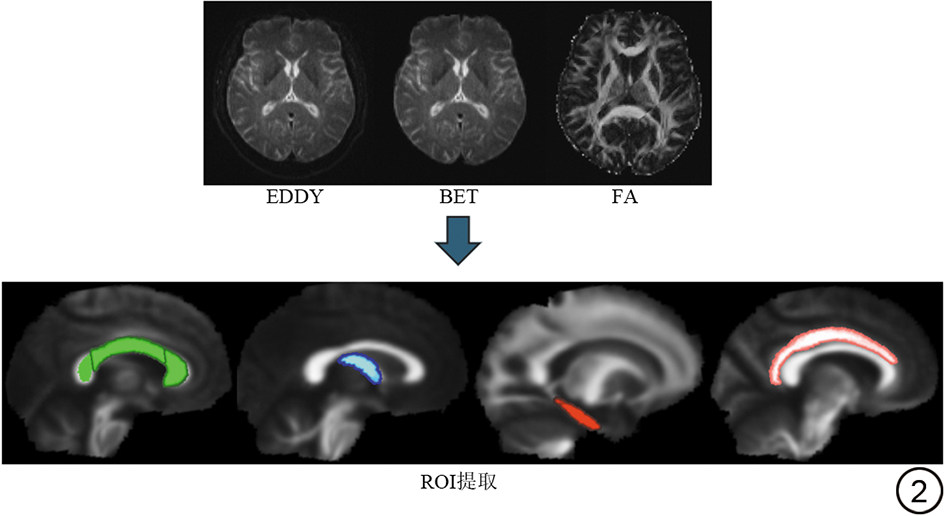

原始DTI数据由磁共振扫描仪输出的DICOM格式经dcm2niix软件(v1.0.2023)转换为NIfTI格式。转换过程中保留原始扩散梯度信息(b值与b向量文件,bval/bvec),并进行数据一致性检查以确保梯度方向正确匹配。DTI数据的预处理与参数计算在FMRIB Software Library(FSL, Version 6.0.5, Oxford, UK)平台中完成。首先,使用eddy模块对所有弥散加权图像进行头动与涡流畸变校正,以减少受试者运动及梯度切换引起的几何畸变。随后,应用BET进行颅骨剥除,去除非脑组织信号并获得高质量的脑组织掩膜。经校正与剥除后的数据通过dtifit模块进行DTI拟合,计算各体素的主要弥散参数,包括各向异性分数(fractional anisotropy, FA)、平均弥散率(mean diffusivity, MD)、轴向弥散率(axial diffusivity, AD)及径向弥散率(radial diffusivity, RD)。数据分析采用基于感兴趣区(region of interest, ROI)的方法进行群体统计。本研究基于约翰霍普金斯大学ICBM-DTI-81白质图谱(https://fsl.fmrib.ox.ac.uk/fsl/fslwiki/Atlases),采用假设驱动的ROI分析策略,只从上述图谱中重点选取了既往文献中反复报道且与AD及aMCI密切相关的关键白质区域(双侧穹窿、胼胝体以及海马旁回扣带纤维)[3, 4, 5]共10个ROI进行分析(图2)。对于每位受试者,计算其配准至标准空间后的FA、MD、AD及RD图在各ROI掩膜内的平均值,这些参数均作为后续统计分析的指标。

图2  DTI数据预处理流程及基于JHU-ICBM-DTI-81图谱的ROI定位示意图,上排依次为EDDY校正图、BET(颅骨剥离图)及平均FA图;下排显示ROI提取结果,其中绿色为胼胝体、蓝色为穹窿、红色为海马旁回扣带纤维、粉色为扣带回。DTI:弥散张量成像;ROI:感兴趣区;FA:各向异性分数。

Fig. 2  DTI preprocessing workflow and ROI localization based on the JHU-ICBM-DTI-81 white matter atlas. Top row: EDDY-corrected image, BET skull-stripped image, and mean FA map. Bottom row: ROI extraction results, with green indicating the corpus_callosum, blue the fornix, red the Cingulum_hippocampus, and pink the Cingulum_cingulate_gyrus. DTI: diffusion tensor imaging; ROI: region of interest; FA: fractional anisotropy.